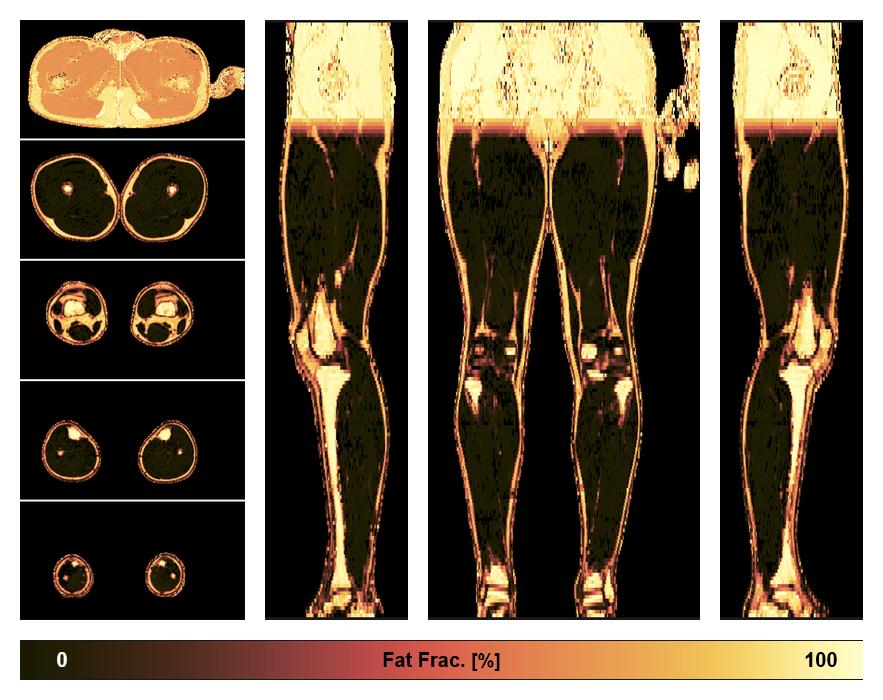

• Fat fraction

The fat fraction of the lower extremity obtained from the dixon reconstruction for muscle water fat quantification.

• R2 star relaxation

The R2 star relaxation time of the lower extremity obtained from the dixon reconstruction for muscle water fat quantification.